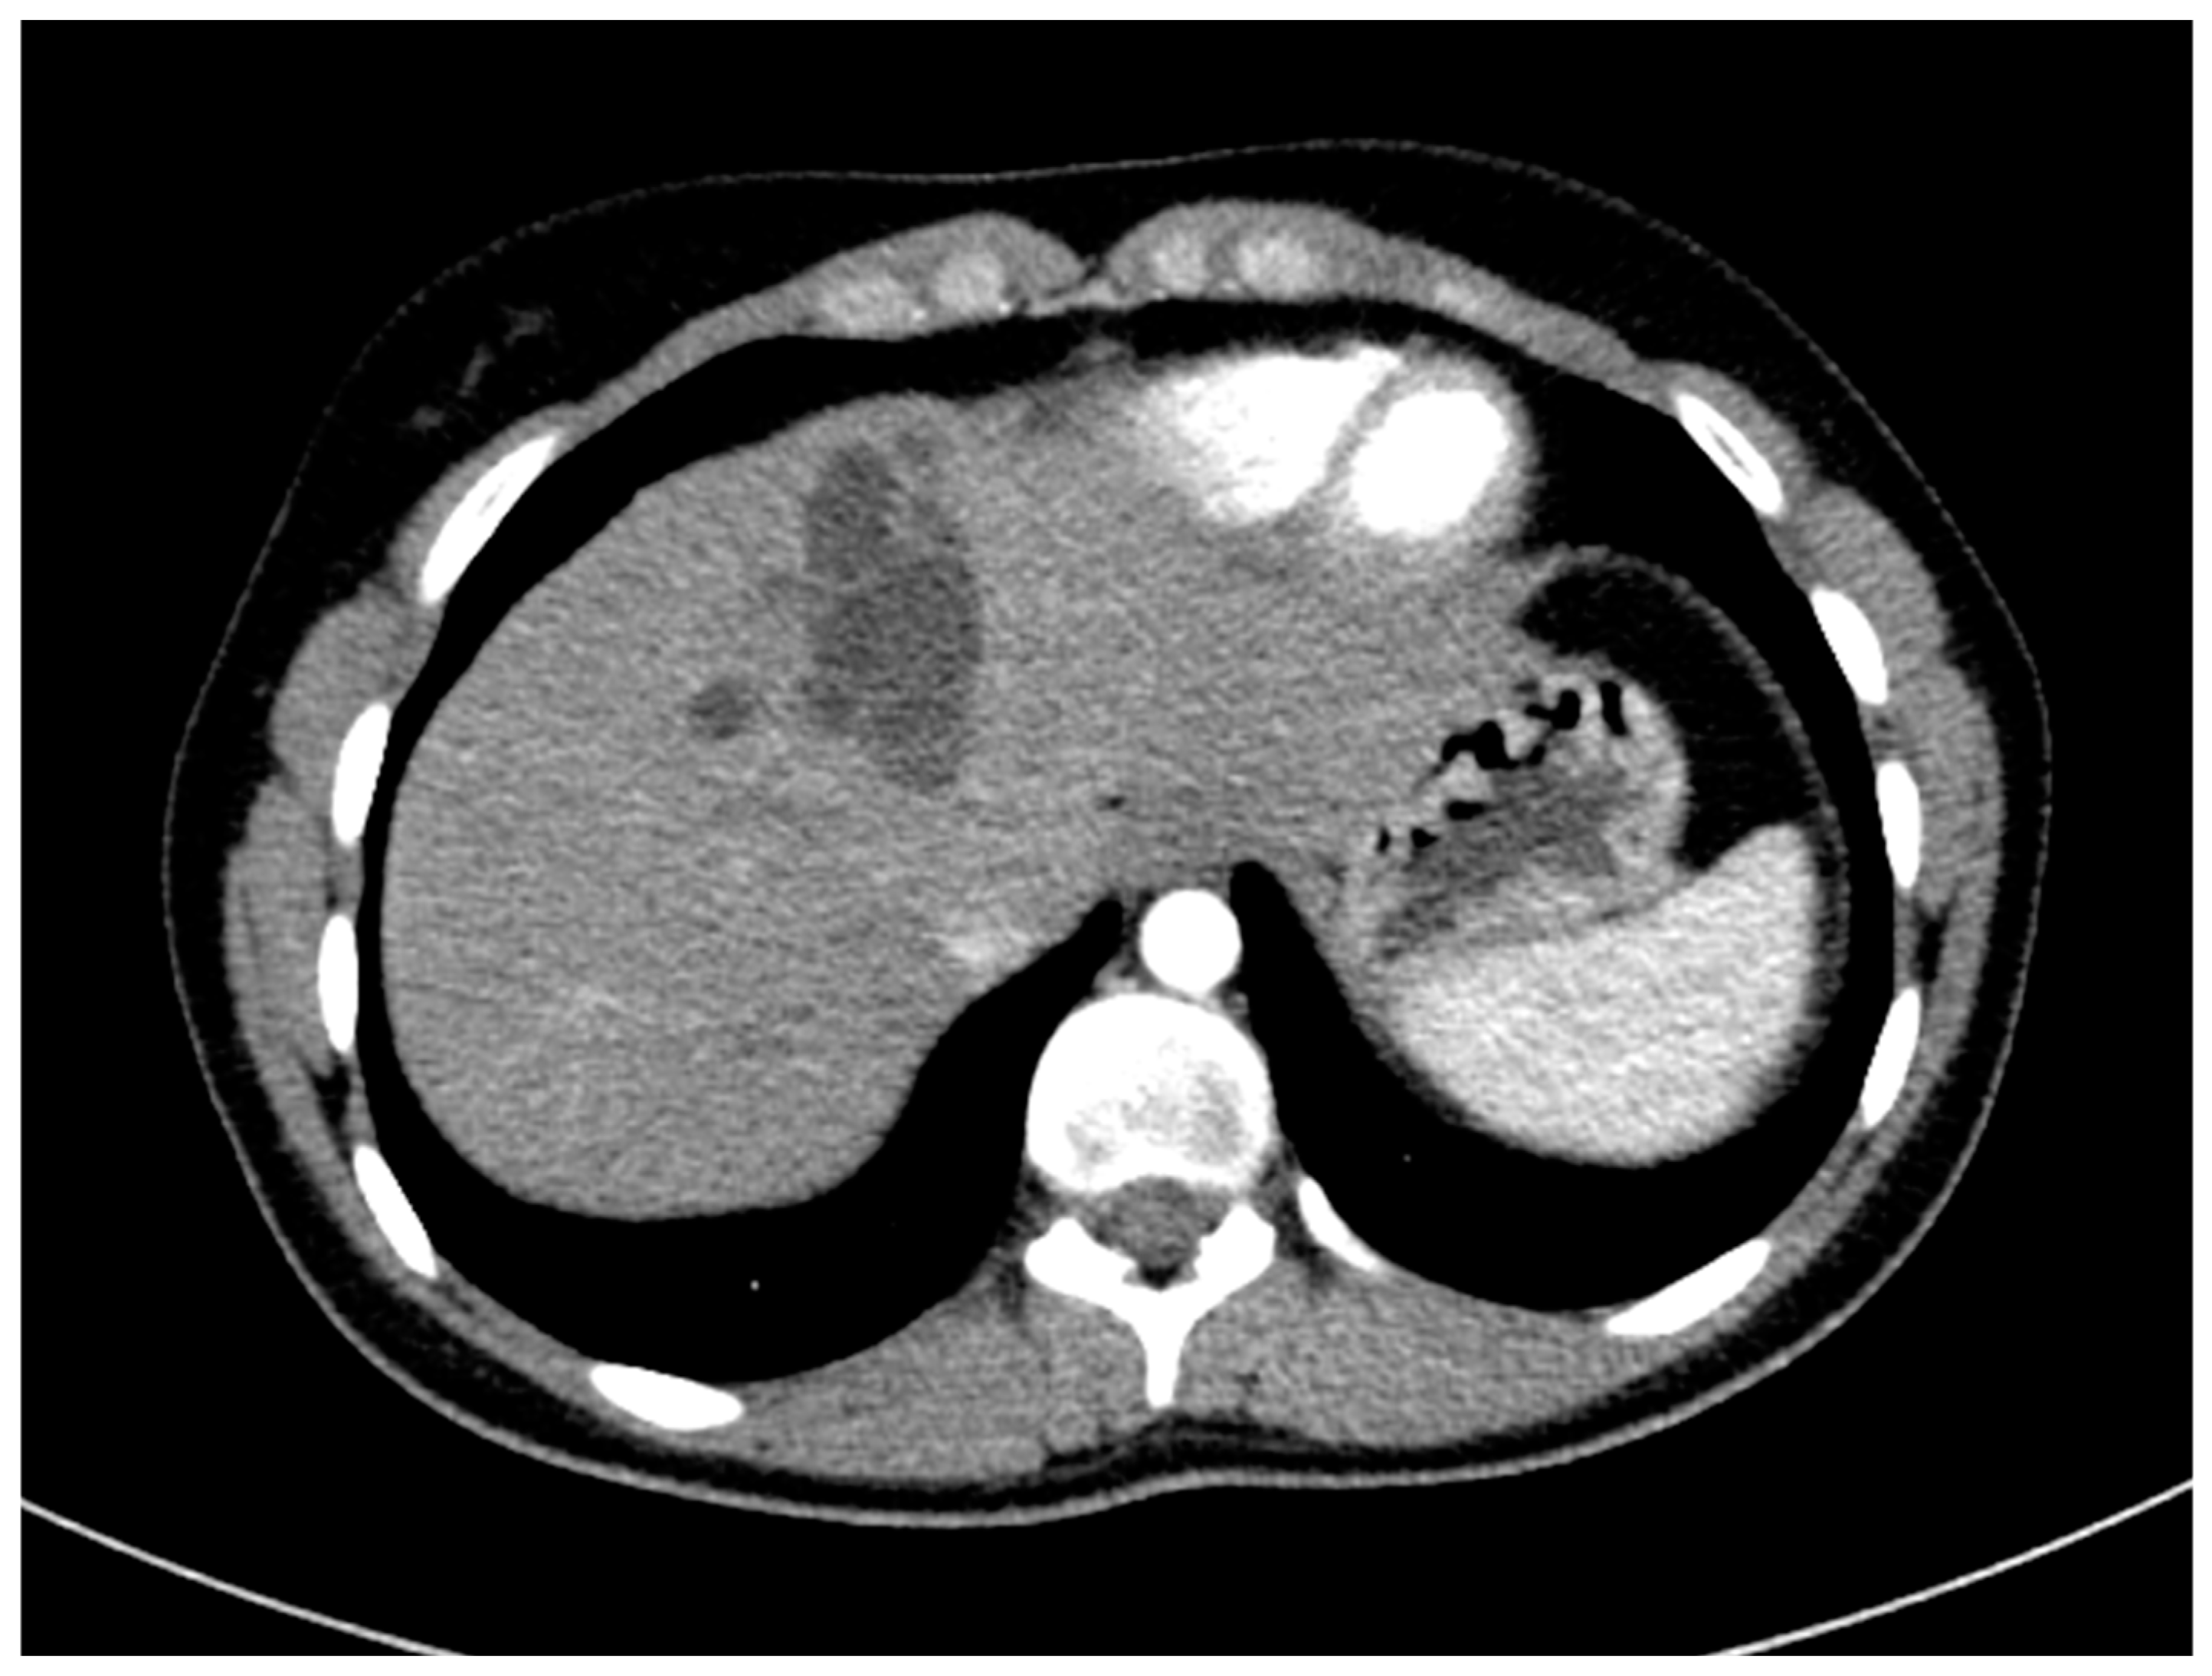

The surgical department decided not to opt for a surgical resection due to difficult access to the cyst, and therapy with the antihelminthic medication albendazole for four weeks was initiated. Additional diagnostics, including chest CT and an MRI scan of the brain, did not find any further extrahepatic manifestations of the hydatid disease. The chest CT scan included parts of the abdomen and also depicted the cyst and lower-attenuated daughter cysts (Figure 6).

Figure 6.

CT imaging shows a large hydatid cyst in segment IV, classified as WHO type CE2. The main cyst has slightly higher attenuation compared to the smaller peripheral daughter cyst.